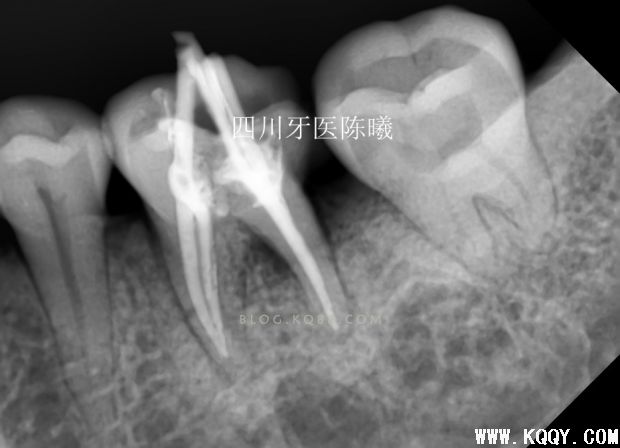

到了这,大家可能以为结束了,对不起,还要耽误您再看看,后面还有,前面我提到这个患者处理了两颗牙,36在观察3天后出问题,很不辛,今天根充前患者告知46肿了,一看也出问题了~先上照片

从这两张照片可以发现46的问题,没有办法,很遗憾告知病人这个暂充失败,也只有根管治疗,患者觉得除了肿,没有疼痛,甚至可以吃东西,不愿意治疗,经过耐心口腔宣教以及女儿劝告后同意治疗!感谢患者家属帮忙啊!

由于在检查时发现46远中龈乳头红肿,仔细检查后感觉以前暂充物有悬突,所以在开髓时一并去净!